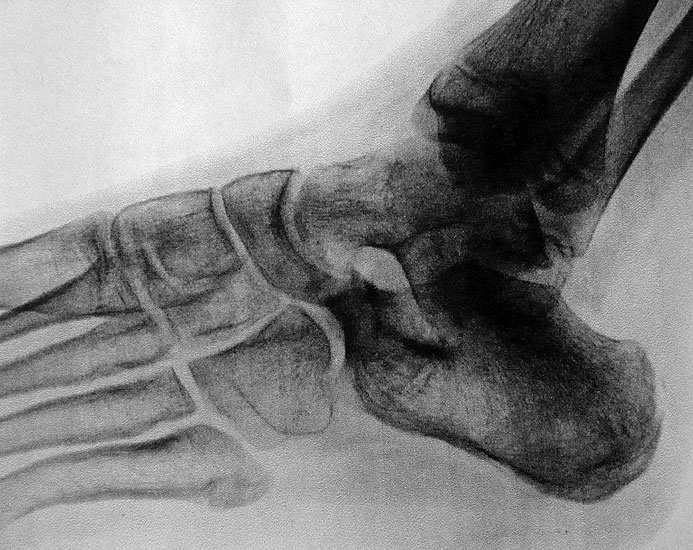

Die bildgebende Primärdiagnostik ist die Röntgen-Übersichtsaufnahme des Fußes im seitlichen, dorsoplantaren und schrägen Strahlengang. Weitere in der Literatur beschriebene Röntgen-Spezialeinstellungen sind durch die modernen dreidimensionalen Verfahren überholt.

In der Bildgebung ist bei dieser Form häufig eine einfache Röntgenschrägaufnahme (Abb. 8) ausreichend. Kombinationen mit talocalcanearer Coalitio werden beobachtet und sollten im Verdachtsfall ausgeschlossen werden. Für die Therapie wesentlich ist im Jugendlichen- und Erwachsenen-Alter das Ausmaß der degenerativen Veränderungen im Bereich des Talonavicular-Gelenkes.

Diagnostisch sollte neben Röntgenübersichtsaufnahmen (indirekte radiologische Zeichen: Dorsaler Traktions-Osteophyt am Taluskopf, „talar beaking“; kontinuierliche Linie der Trochlea-tali-Kontur übergehend in die Sustentaculum-tali-Kontur, „C-Zeichen“ (Abb. 11) 10) immer die dreidimensionale Bildgebung eingesetzt werden. Das MRT (mit Kontrastmittel) kann die Struktur der Brückenbildung und z.B. die Qualität des Restgelenkes (Knorpel-Dicke) besonders gut abbilden; das Dünnschicht-CT zeigt die knöcherne Feinstruktur im Bereich der Coalitio und den oft sehr schrägen Spalt-Verlauf im Frontalschnitt dagegen häufig genauer. Meist findet sich die Überbrückung im Bereich der medialen Facette; die Schichten sollten jedoch bis weit nach dorsal beurteilt werden, da ansonsten dorsomediale Formen übersehen werden können. Rozansky et al 7 unterschieden fünf morphologische Typen auf der Basis von 3-D-CT-Rekonstruktionen. Allerdings ist eine prognostische Zuordnung bisher nicht möglich.